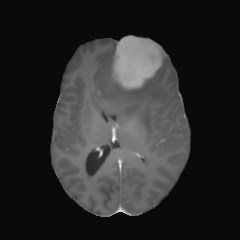

| non-CE T1w (Input) | Residual U-Net (PM) | RF Baseline | PMRF (ours) | CE T1w (GT) |

We qualitatively evaluate the top-performing Residual U-Net (Posterior Mean), RF baseline, and PMRF models (with a patch-overlap of 32 for all and integration steps for the RF baseline as well as the PMRF model) on the held-out test set. For a set of representative cases, Figure 3 compares the non-CE T1w input, Res. U-Net (equivalent to PM), RF baseline, our two-stage PMRF, and the ground truth CE T1w image. Example 1 depicts a metastases patient, example 2 a high-grade glioma patient, and example 3 a meningioma patient. Across these test cases, the Res. U-Net output accurately localizes lesions and captures their overall enhancement intensity but appears overly smooth, and muted in rim heterogeneity and fine texture. The Stage 2 PMRF refinement consistently sharpens lesion boundaries, reinstates subtle vascular and margin details, and restores characteristic enhancement patterns, yielding synthetic images nearly indistinguishable from true post-contrast scans. However, Stage 2 can only refine what the posterior-mean predictor already suggests. If a subtle rim, micro-metastasis, or vessel enhancement is entirely suppressed in Stage 1, Stage 2 has no signal to resurrect it; its perturbations stay within a narrow neighborhood of the Stage 1 output. In contrast, the RF baseline directly predicts the CE signal from the perturbed non-CE image. However, this comes with the limitation of not predicting the CE strength faithful or missing subtle details as in examples 2 and 3.